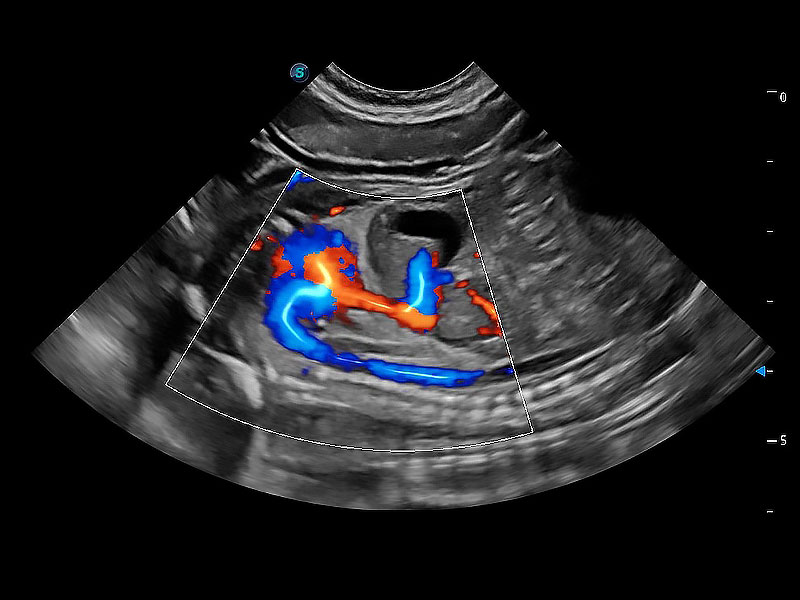

• Micro F 显微血流成像

极大提升超低速微细血流的检出能力,同时更精准地滤除软组织和超声信号,为兽用医生提供以往无法通过常规血流获得的疾病诊断信息。

• Bright Flow 立体血流成像

在传统二维血流成像的基础上,呈现血流的立体感,具有动感的生命力之美。即便是微小的血管也能轻松应对,提高了血流的视觉敏感性。

(犬)胎儿主动脉弓立体血流

(犬)胎儿四腔心

(犬)二腔心血流